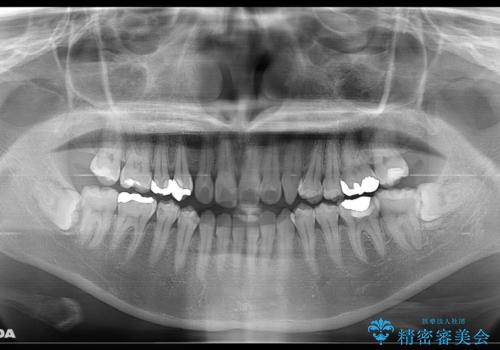

- 受け口で、前歯の嚙み合わせが気になるとの事でご相談にいらした方です。先天的に右上犬歯がなく、左上犬歯も小さい状態でした。矯正治療にて周囲の歯を動かして歯のスペースを確保した上で、被せものにて歯を作っていきました。

歯科技工士さんの熟練した技術により、周囲の歯としっかりなじむ天然歯のような被せ物をお作りすることが出来ました。

矯正治療と補綴治療をうまく組み合わせることで、美しい口元に仕上げることが出来ました。矯正治療、補綴治療をまとめて行える総合歯科治療を体現した治療といえます。